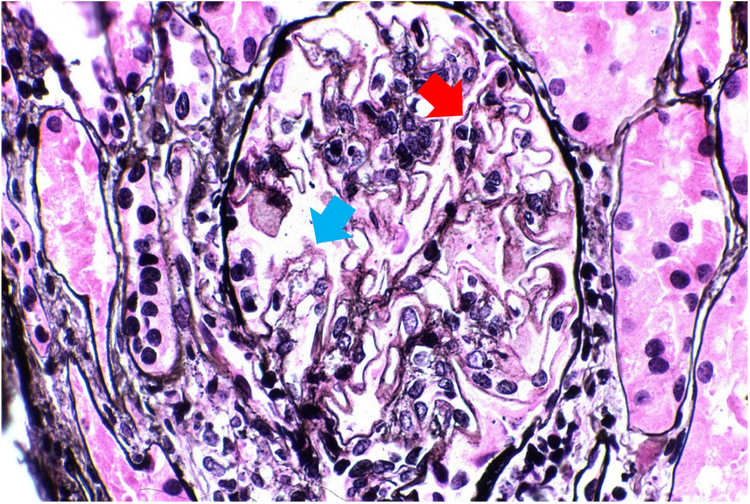

Dans la figure 2, les échantillons de patients à un stade avancé de NL (classe 5) présentent quant à eux des trous diffus (flèche bleue) et de petites pointes (flèche rouge) le long des membranes basales glomérulaires.3